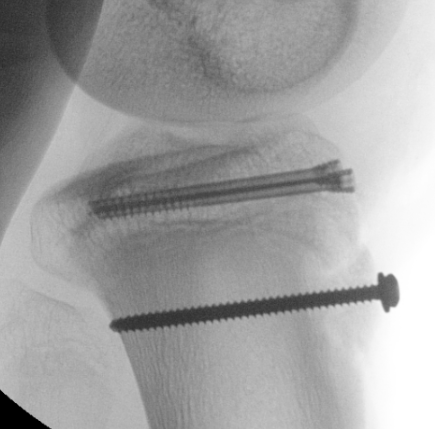

Type III

Technique

Restore articular surface

- may need to visualize joint line with arthrotomy / arthroscopy

- pass guide wires for screws into epiphysis and tibial tubercle

- image intensifer to ensure reduction / growth plate protection / no penetration to posterior neurovascular structures

- secure with AP screws in tibial epiphysis through vertical split in patella tendon

- unicortical fixation to protect popliteal artery

- restore tibial tuberosity with screws +/- washer

Results

Union

- systematic review of 956 cases

- 88% managed with surgery

- union in 954/956 (99.8%) of fractures